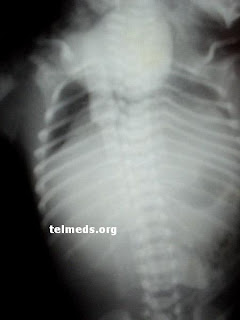

Ectopia Cordis

Ectopia Cordis is a rare disease with incidence of 5.5 to 7.9 cases per million births. Until 2001, 267 cases have been reported, most of them (95%) associated with other heart diseases. We studied heart disease of 6 cases of Cordis ectopia. Depending on the affected area, patients with Cordis ectopia classified into 4 types: cervical, chest, thoracoabdominal, and abdominal. The 6 patients described died before 3 days of life, four of them at birth. Three belong to the group of ectopia chest and three to the chest and abdomen. All had a ventricular septal defect in the third ventricle (50%) and tetralogy of Fallot, pulmonary atresia in the other 3 (50%). In 2 hearts with double outlet mitral valve involvement, valve stenosis and parachute mitral valve atresia. This type of anomaly has not been described previously.

Patients with serious heart disease of ectopia Cordis, most of them is troncoconal anomalies. Two of our patients have a defect that was not previously described. Although several attempt was made such as surgery, the survival of patients with this heart disease is very low, and most of them die within the first week of life.